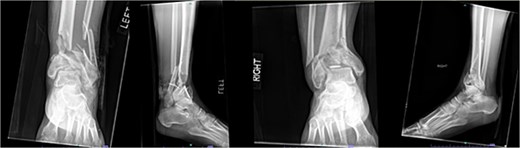

A 57-year-old male with a body mass index (BMI) of 48.7 kg/m2 and multiple comorbidities, including asthma, coronary artery disease, hypertension, hyperlipidemia, ischemic cardiomyopathy, obstructive sleep apnea, and hypothyroidism, following a motor vehicle collision when he lost control of his vehicle due to a coughing spell. His injuries included bilateral pilon fractures (Fig. 1), a T2 superior endplate fracture, and bilateral pulmonary contusions. He initially presented to a regional hospital and was transferred to our facility 10 days after the injury.

Anterior-to-posterior (AP) radiographs of patient 1 obtained 10 days after injury, upon transfer to our facility, demonstrating bilateral pilon fractures.